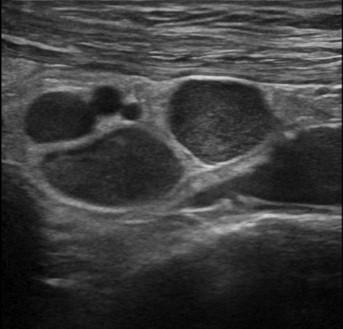

Viêm ruột

» Thông tin: Nữ giới – 55 tuổi.

» Lâm sàng: Tiêu chảy.